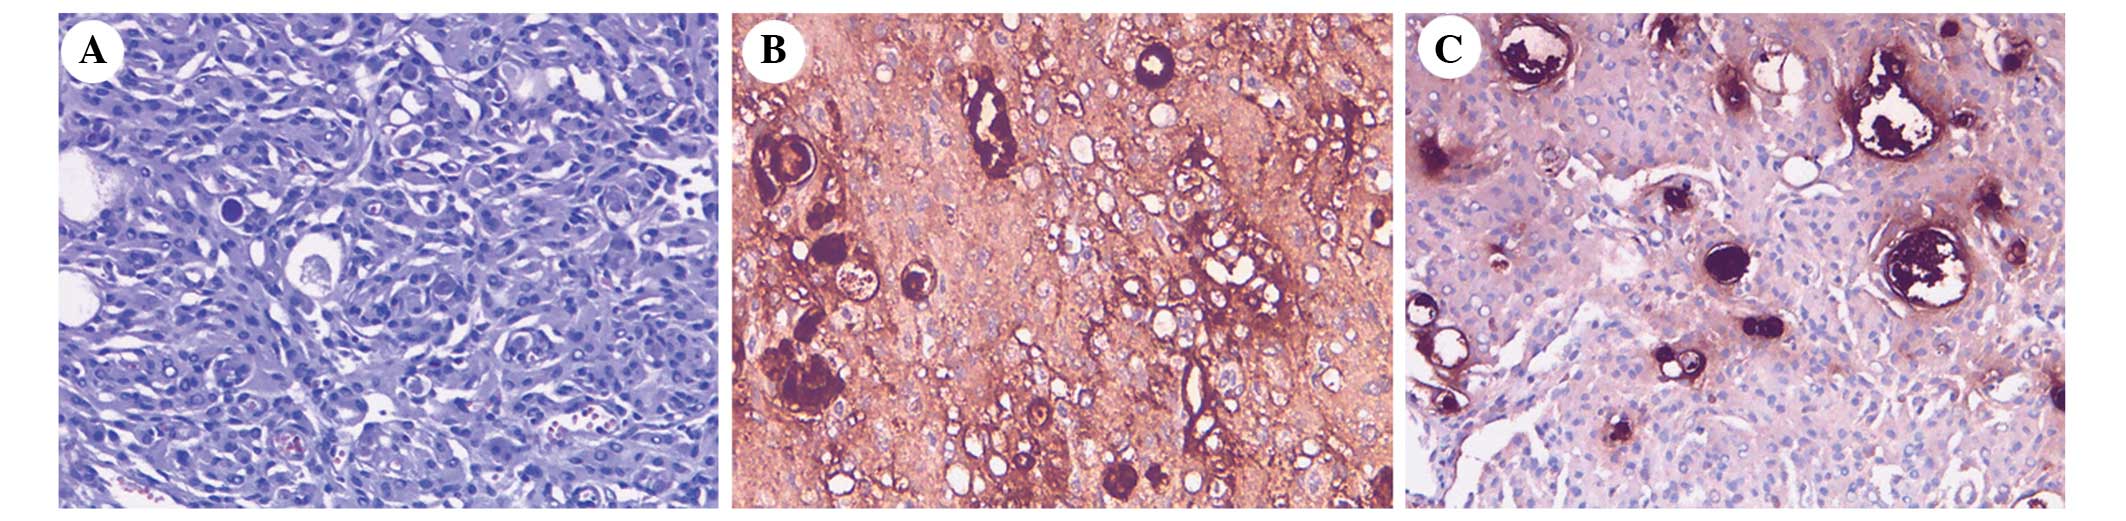

Following histological analysis of the specimens, it was noted that the SFT was composed of proliferating spindle cells (Fig. 3A). Immunohistochemistry determined that the SFT cells were positive for cluster of differentiation (CD)34, vimentin, B-cell lymphoma 2 (Bcl-2) (Fig. 3B) and CD117, and negative for epithelial membrane antigen (EMA) (Fig. 3C) and S-100, with a Ki-67 proliferation labeling index of ~2.5%. Histological examination of the secretory meningioma demonstrated evidence of multifocal epithelial cell differentiation and an intraepithelial microcavity containing eosinophil pseudopsammoma bodies (Fig. 4A). Immunohistochemistry determined that the secretory meningioma cells were positive for EMA (Fig. 4B), vimentin and carcinoembryonic antigen (Fig. 4C), with a Ki-67 proliferation labeling index of ~2.3%. Periodic acid-Schiff staining was positive. No complications appeared following surgery. The patient was followed-up at 4 and 8 months and every 12 months subsequent to surgery. At the 8-month follow-up, there were no signs of recurrence.

Figure 3.

(A) Histological examination determined that the solitary fibrous tumor was composed of proliferating spindle cells (staining, hematoxylin and eosin). Immunohistochemistry demonstrated that the tumor tissue was (B) positive for B-cell lymphoma 2 (magnification, ×100) and (C) negative for epithelial membrane antigen (magnification, ×100).